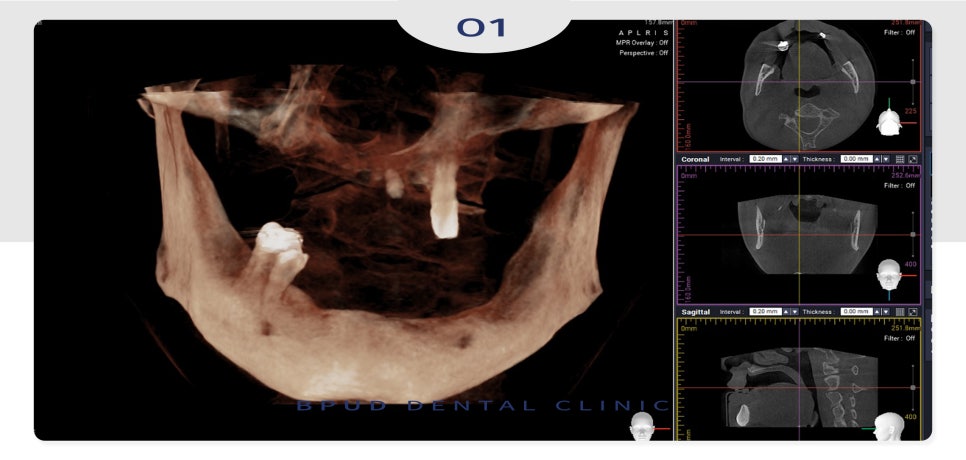

옆에서 보았을 때와 위쪽 뼈를 본

CT인데요.

따라서 입술이 들어가 보이는 것을

방지하고, 심미성을 고려하여

현재 남아 있는 자연치들을 모두 발치하고

위쪽에 임플란트 5개, 아래쪽에 4개를

식립하여 하이브리드 고정성 틀니를

진행하기로 하였습니다.